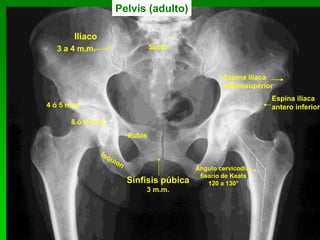

Pelvis (adulto)

4 ó 5 m.m.

8 ó 9 m.m.

Sínfisis púbica

3 m.m.

Ilíaco

Pubis

Espina ilíaca

anterosuperior

antero inferior

Sacro3 a 4 m.m.

Ángulo cervicodia-

fisario de Keats

120 a 130°

23 Pelvis (adulto) 4 ó5 m.m. 8 ó 9 m.m. Sínfisis púbica 3 m.m. Ilíaco Pubis Espina ilíaca anterosuperior Espina ilíaca antero inferior Sacro3 a 4 m.m. Ángulo cervicodia- fisario de Keats 120 a 130°